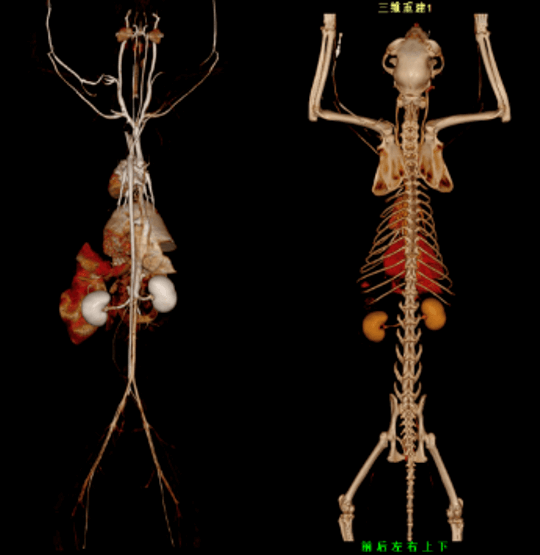

臨床畫廊